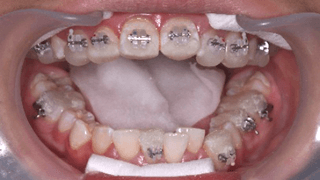

2

治療計画を立ててカウンセリング後、治療を開始します。ブラケットを歯に接着して、形状記憶合金のワイヤーを装着します。右上第一小臼歯を抜歯しています。